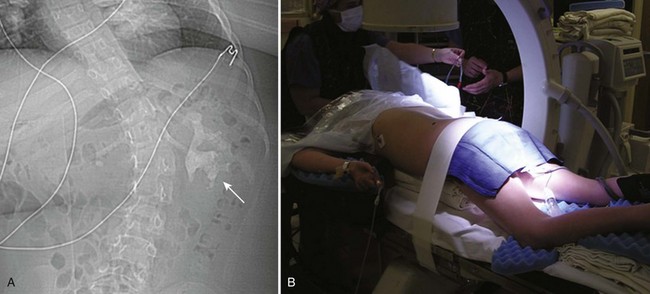

Much planning is required prior to embarking on PCNL in children. Films must first be reviewed scrupulously to determine if the stone(s) is/are amenable to a percutaneous procedure. Nephrocalcinosis in children, for example, may be confused with staghorn calculi; the etiology and treatment are very different (Fig. 135–8). Infection is the most common causative agent in the formation of a staghorn calculus, and PCNL is a first-line therapy. The most frequent causes of nephrocalcinosis are hereditary tubulopathies and vitamin D intoxication (Ammenti et al, 2009). Medullary sponge kidney is a renal malformation characterized by cystic anomalies of precalyceal ducts, which is frequently associated with nephrocalcinosis and stone formation (Gambaro et al, 2006). Nephrocalcinosis is most often not amenable to successful endourologic treatment(s) because calculi are intraparenchymal and thus outside the collecting system. Management is often medical and aimed at prevention of further nephrocalculi, a cause of worsening renal function.

Figure 135–8 A 9-year-old boy with cerebral palsy and gross hematuria. CT scan demonstrated bilateral nephrolithiasis (A) thought to be staghorn calculi. Plain radiograph (B) and bilateral retrograde pyelograms (C and D) correlate to show nephrocalcinosis (white circles and white arrows, respectively) reflective of medullary sponge kidney disease. Subsequent metabolic workup revealed renal tubular acidosis (RTA) with hypercalciuria.